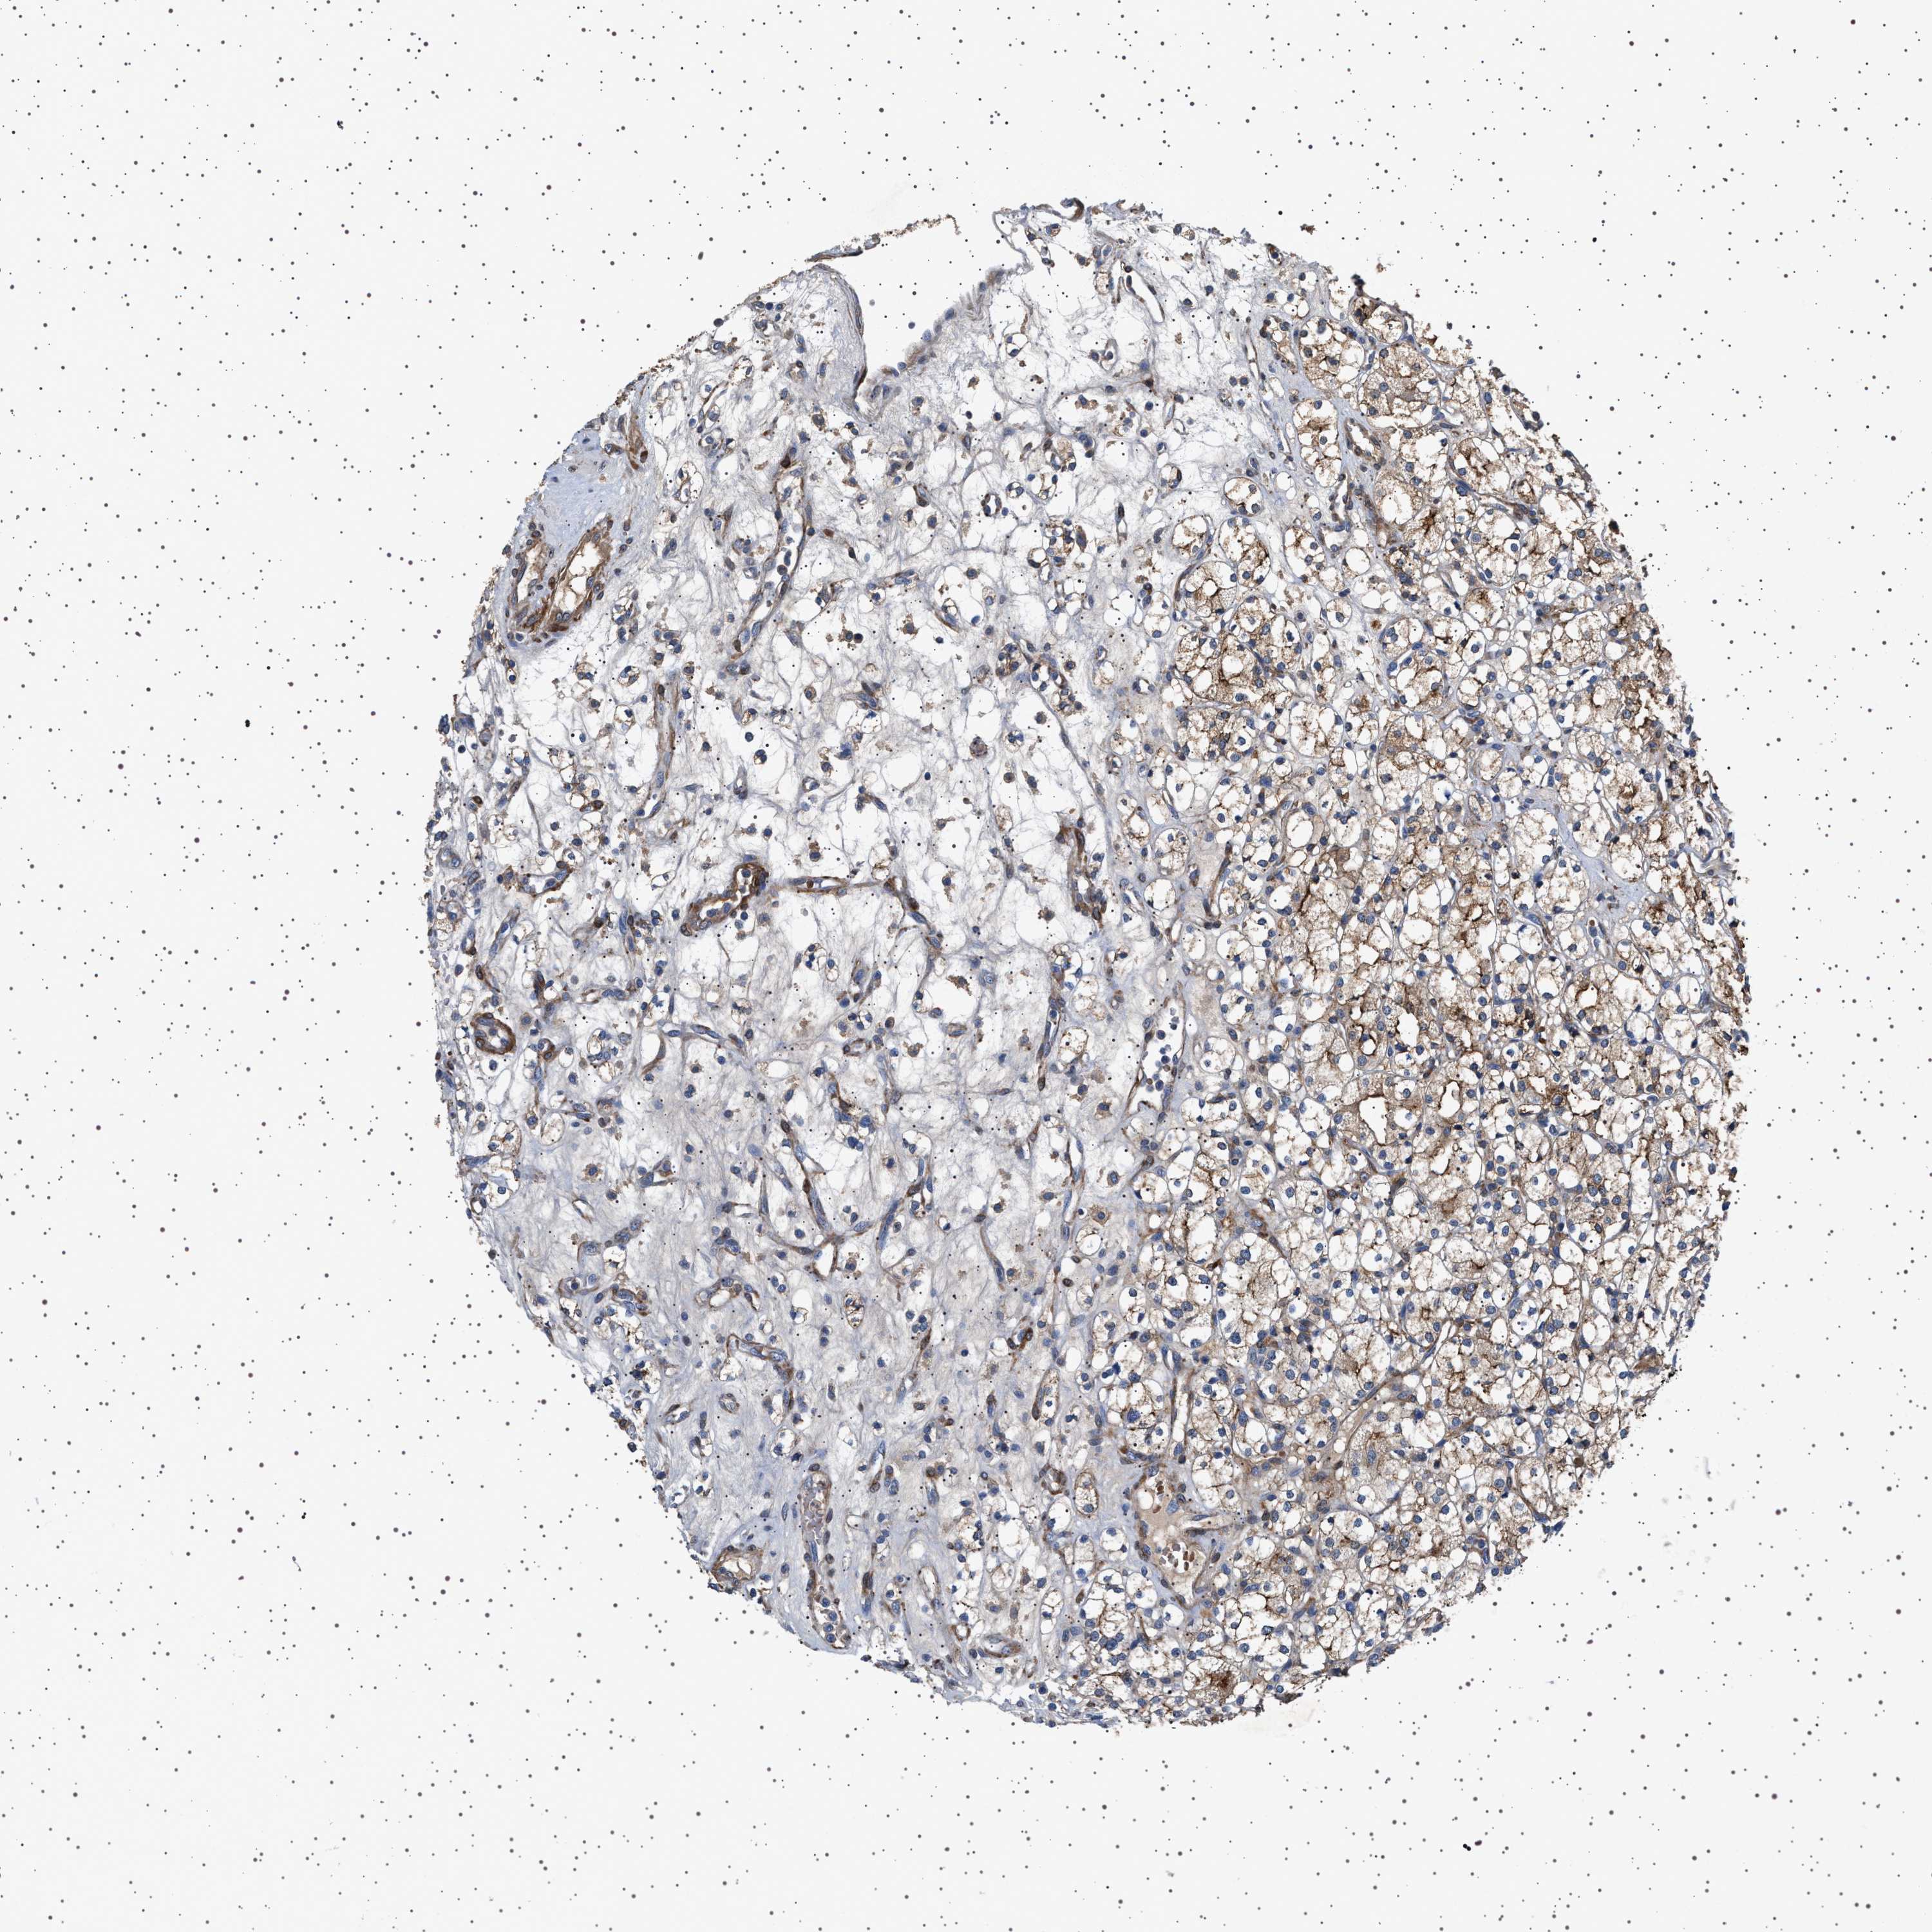

CANCER RENAL CANCER Show tissue menu

KICH TCGA KIRC TCGA KIRC VALIDATION KIRP TCGA PROTEIN RCC CPTAC PROTEIN EXPRESSION

KIDNEY CHROMOPHOBE (TCGA) - Interactive survival scatter ploti

The Survival Scatter plot shows the clinical status (i.e. dead or alive) for all individuals in the patient cohort, based on the same data that underlies the corresponding Kaplan-Meier plots. Patients that are alive at last time for follow-up are shown in blue and patients who have died during the study are shown in red.

The x-axis shows the expression levels (FPKM) of the investigated gene in the tumor tissue at the time of diagnosis. The y-axis shows the follow-up time after diagnosis (years). Both axes are complimented with kernel density curves demonstrating the data density over the axes. The top density plot shows the expression levels (FPKM) distribution among dead (red) and alive patients (blue). The right density plot shows the data density of the survived years of dead patients with high and low expression levels respectively, stratified using the cutoff indicated by the vertical dashed line through the Survival Scatter plot. This cutoff is automatically defined based on the FPKM cutoff that minimizes the p-score. The cutoff can be changed by dragging the vertical line or by entering a cutoff value in the square labeled "Current cut-off".

Under the Survival Scatter plot the p-score landscape (black curve; left axis) is shown together with dead median separation (red curve; right axis). Dead median separation is the difference in median mRNA expression between patients who have died with high and low expression, respectively. It is calculated as follows: median FPKM expression of dead patients with high expression - median FPKM expression of dead patients with low expression. This is intended to aid the user in visually exploring custom cutoffs and the associated p-scores and dead median separation.

Individual patient data is displayed and can be filtered by clicking on one or more of the category buttons on the top of the page. Categories describing expression level and patient information include: high, low, alive, dead, female, male and tumor stages. The scale of the x-axis can be toggled between linear and log-scale by clicking on the "x log" button. Mouse-over function shows TCGA ID, patient information and mRNA expression (FPKM) for each patient.

& Survival analysisi

Kaplan-Meier plots summarize results from analysis of correlation between mRNA expression level and patient survival. Patients were divided based on level of expression into one of the two groups "low" (under cut off) or "high" (over cut off). X-axis shows time for survival (years) and y-axis shows the probability of survival, where 1.0 corresponds to 100 percent.

GUCY1B1 is not prognostic in Kidney Chromophobe (TCGA)